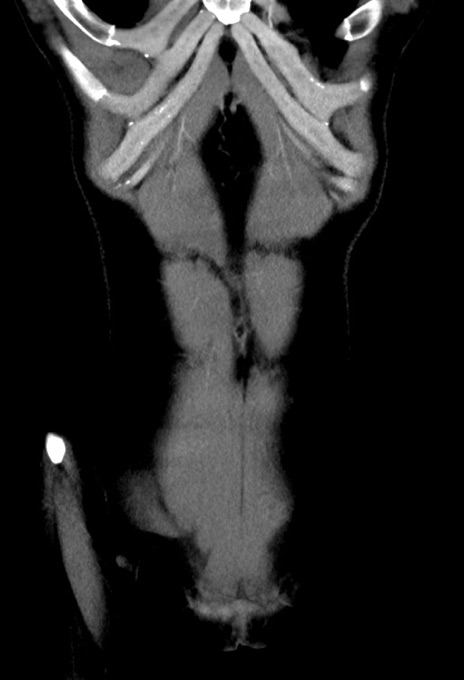

症例17(冠状断像)

【症例】20歳代女性

【主訴】嘔吐、下腹部痛

【現病歴】昨日夕食後に嘔吐し下腹部痛が出現。本日になっても嘔吐持続し改善しないため来院。

【身体所見】意識清明、BT 37.2℃、BP 108/67mmHg、腹部:平坦、やや硬、下腹部正中から右にかけて圧痛あり、反跳痛軽度あり、tapping pain(+)。

【データ】WBC 13600、CRP 14.94